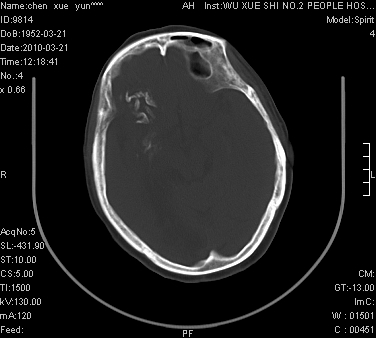

性别:不详;年龄:58岁;病史:不详。

ct表现:1、右侧额颞叶深部不规则钙化密度团块,呈弯曲条带状,占位效应不明显,考虑少枝胶质细胞瘤可能性大于血管瘤。2、右枕叶大片不规则低密度影,密度近似于脑脊液,右侧侧脑室后角及三角区扩张,考虑为陈旧性脑梗塞。

讨论:1、这个病灶的钙化有点像脑回样钙化,因此我最初考虑颅面血管瘤病(sturge-weber综合征),但是查阅了我们网站上的几个颅面血管瘤病病例,钙化均位于脑实质表面,沿脑回分布,而这例病灶位置较深,因此可以否定“颅面血管瘤病”这个诊断。

2、卜一会员曾经说过:少枝胶质细胞瘤的典型征象为弯曲条带状钙化,可作为定性的可靠征象(http://www.radida.com/news_view.asp?id=5150)

3、血管瘤也可以出现弯曲条带状钙化,但血管瘤多数出现“负占位”效应,即病灶周围的脑室、脑池及脑沟不是受压变窄,而是局限性的增宽。